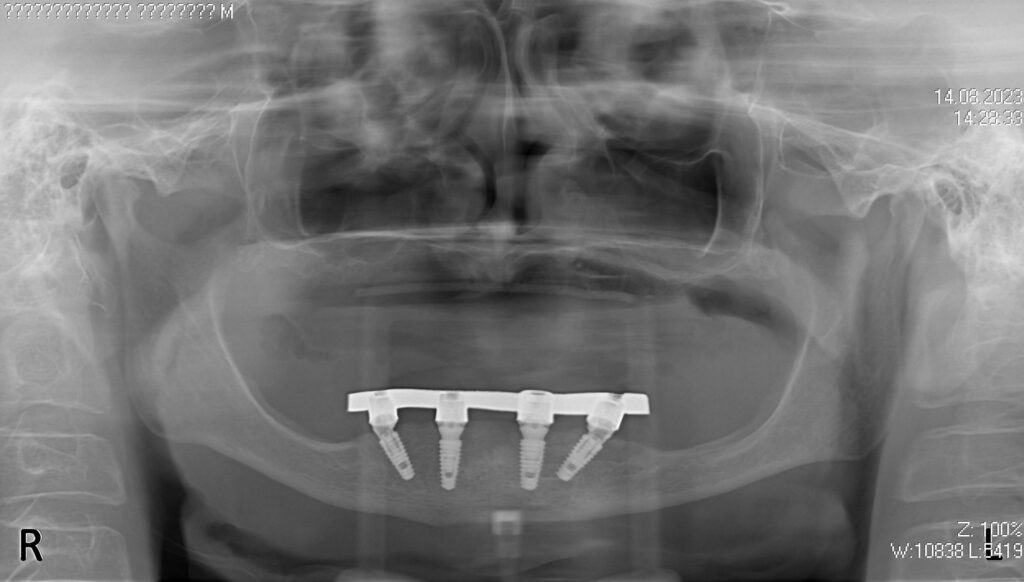

После проведенной консультации было принято решение об удалении зубов на нижней челюсти, которые находились в неудовлетворительном состоянии и проведении комплексной имплантации по системе All-on-4.

После установки 4х имплантантов Megagen Anyone были сняты оттиски для изготовления металлоакрилового протеза на нижней челюсти и для съемного протеза на верхней.

Спустя 7 дней на нижней челюсти зафиксирован металлоакриловый протез из 12 зубов с опорой на 4 дентальных имплантата.